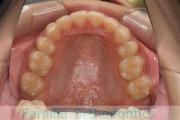

No.23V-132

- 主な症状:

- 開咬

- 年齢:

- 16歳

- 性別:

- 男性

- 抜歯部位

- 上:

- 88

- 下:

- 主な使用装置:

- FEA

- 治療にかかった費用:

- 87万円

開咬なので治療したいとのことで来院されました。受け口傾向のある開咬(前歯が咬み合わない)でしたので、下の親知らずを抜歯してマルチブラケット法にて治療を行いました。約1年半、20回程度の通院が必要でした。開咬は舌の癖の影響が強く、後戻りのリスクが高いケースといえます。